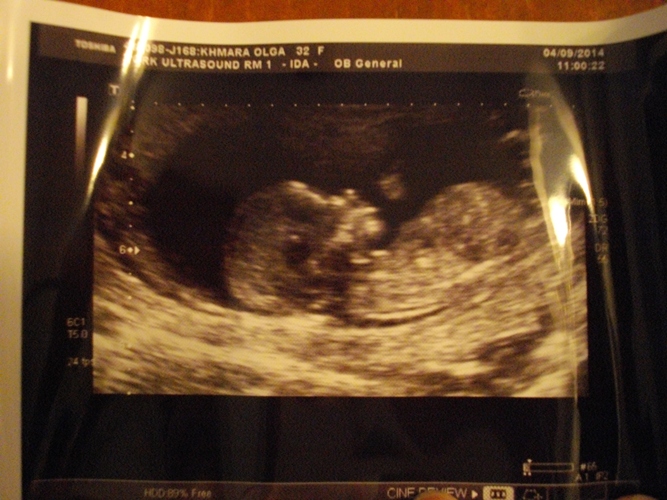

Первый скрининг! Ура, девочки)))

Все хорошо, все показатели в норме, т-т-т. Ростик уже 7,5 см, всвязи с чем ПДР мне передвинули еще поближе и написали на 8 марта)))

Весь прием мой ребенок спал, и как ни пыталась его разбудить тетя-узист, ему/ей было по фиг))) Ножки согнул, рассмотреть, кто в домике живет, даже примерно, не получилось. Может, в следующий раз.

А вот и мы, подросшие и красивые))))